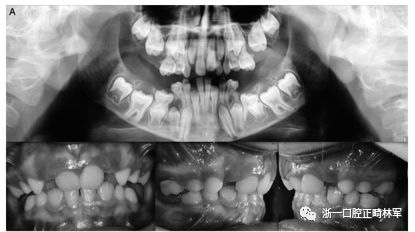

29例中有8例在PTH1R基因中發(fā)現(xiàn)雜合致病變異。表2顯示了本研究中確定的突變概況。簡(jiǎn)言之,在8個(gè)受影響的受試者中有5個(gè)鑒定出三種錯(cuò)義突變,這些受試者以前沒有根據(jù)與已發(fā)表的數(shù)據(jù)庫(kù)的比較(表3)進(jìn)行描述。在兩個(gè)兄弟中鑒定出CTCF結(jié)合位點(diǎn)的變體(c.313×32 A.G rs113566258 SNP)(圖1A,B)。

圖1.(A,B)兩兄弟的口內(nèi)照片。全景:外顯子5的下游變體(CTCF結(jié)合位點(diǎn))rs113566258 SNPc.313±32A>G; 在外顯子16中的變體(位置3:46903467)c.1593-95 Del C,p.531 / 532; 外顯子10中的同義變體(位置3:46899419)c.1152 G>A.

兄弟姐妹被診斷為I型PFE并顯示雙邊呈現(xiàn)。該變體(PTH1R基因的外顯子5的下游c.313×32 A.G)發(fā)生在與轉(zhuǎn)錄因子相互作用的調(diào)節(jié)區(qū)中。除了這種突變之外,這些兄弟還受到第二個(gè)突變的影響,這些突變對(duì)每一個(gè)都是獨(dú)特的:一個(gè)兄弟姐妹(II:1)也存在在外顯子16的基因氨基末端發(fā)生的移碼缺失,c.1593DelC ,第(Pro532Leufs *)(圖1A,B)。在另一個(gè)同胞(II:3)中,鑒定出在蛋白質(zhì)氨基酸序列水平不引起變異的外顯子,c.1152GA(rs200475872;圖1A,B)中的同義變體,但涉及改變含氮堿?;谟?jì)算機(jī)分析,這種改變可能會(huì)影響mRNA的折疊并影響其半衰期和蛋白質(zhì)生產(chǎn)。在這個(gè)患者樣本中,在一個(gè)孤立的病例中發(fā)現(xiàn)了同樣的同義變體c.1152G.A,由于PFE而具有嚴(yán)重的開合(圖2)。

本研究中確定的低咬合的臨床特征與PFE基于基因診斷和萌出障礙診斷標(biāo)準(zhǔn)的應(yīng)用相一致。對(duì)特定相關(guān)牙科特征的仔細(xì)臨床檢查包括以下內(nèi)容:至少一顆牙包括低咬合,局限于后部區(qū)域,單側(cè)(38%;圖1A)和雙側(cè)呈現(xiàn)(35%;圖1B和2),至少有一個(gè)暫時(shí)性后牙(48%暫時(shí);圖1A,B和3A; 55%永久性,圖3B)。此外,觀察到牙面特征如下:由于受影響側(cè)的側(cè)向開放咬傷的嚴(yán)重程度而引起的垂直骨骼不對(duì)稱(35%;圖1A,B和圖3A,B);由下頜骨側(cè)向偏離組成的面部不對(duì)稱(圖1A,B和圖2;表4)。這種不對(duì)稱在單側(cè)開合患者中更為明顯。進(jìn)一步發(fā)現(xiàn)受影響的患者與先前報(bào)道的患者存在上頜骨收縮和III類牙齒/骨骼關(guān)系(28%;圖1A,B和圖2)。至少有一例患者出現(xiàn)了相對(duì)于9名患者的低咬合。表4總結(jié)了PTH1R的表型結(jié)果和相關(guān)的突變分析(N = 8)。